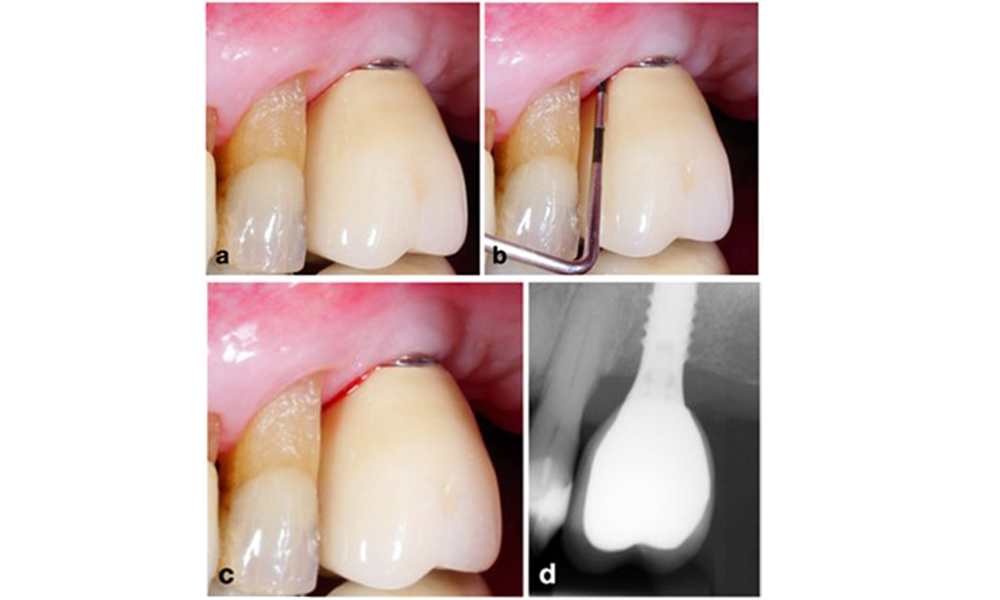

Peri-implantitis is identified by (1) signs of inflammation similar to mucositis, (2) radiographic evidence of bone loss after initial healing and (3) an increase in probing depth compared to measurements taken shortly after placing the prosthetic reconstruction (figure 2). In the absence of previous radiographs, radiographic bone level of ≥ 3 mm along with bleeding on probing and probing depths ≥ 6 mm, indicates peri‐implantitis.

The expected bone loss after initial healing attributed to marginal bone remodelling, varies based on factors such as the implant system or type. For instance, 1–2 mm bone loss is generally considered “normal” for bone level implants with an external connection (figure 2d, implant in position 23).